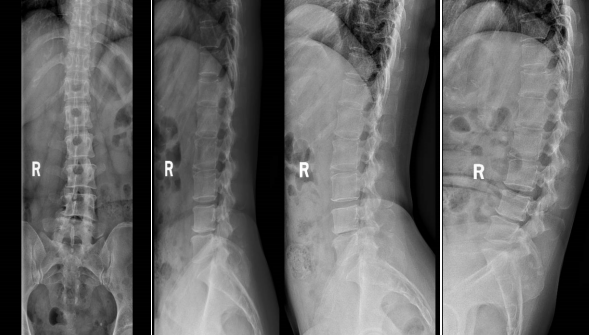

▲①术后腰椎正侧位及过伸过屈位X线片

术后第一天,医生为谭阿姨伤口换药并为他进行了腰椎X线及CT复查,显示手术后内固定植入物固定良好,椎间融合器放置在位,下肢麻木及疼痛症状明显好转。经过一系列的康复锻炼,谭阿姨术后第二天下床行走,术后5天办理出院。